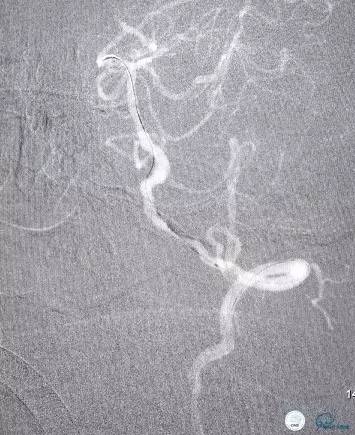

术前DSA(图7-8):右侧椎动脉颅外段纤细,非优势供血,颅内段以远未见显影;左侧椎动脉颅内段PICA动脉以远次全闭塞(狭窄率约为95%以上),基底动脉缓慢浅淡显影,双侧大脑后动脉未见显影。左侧前循环通过后交通动脉向后循环部分区域代偿供血。

图7

图8